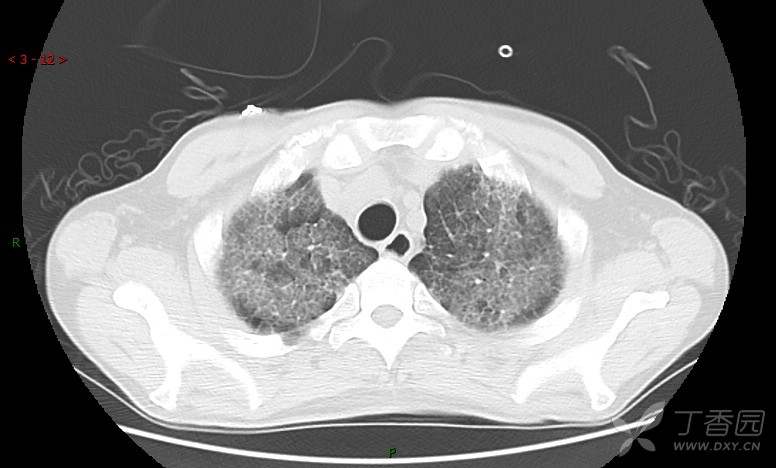

地图+铺路石征=PAP?那升高的CEA怎么说(病例3连发,附其他2例链接)

患者男,42岁,咳嗽半年余,加重伴憋喘2月余。

患者半年余前无明显诱因出现间断咳嗽,干咳为主,偶咳少量黄白痰,剧烈咳嗽或运动后可出现轻度憋喘,无高热、脓臭痰,无胸痛、咯血及晕厥,无低热乏力及盗汗,无心前区压榨感及夜间阵发性呼吸困难,初未在意,未予正规诊治。2月余前患者自觉上述症状较前加重,咳嗽、憋喘明显,黄白色粘痰略有增多,伴有发热,热前伴有畏寒、寒战,体温最高达38.9℃,先后就诊多家医院,入住重症监护室,未行气管插管,考虑“重症肺炎”,给予“美罗培南、复方磺胺甲噁唑”等药物抗感染,“卡泊芬净”抗真菌,并给予“甲泼尼龙”等药物治疗35天,经治疗后症状好转于2018-04-02出院。患者自出院后仅应用中药治疗(具体不详),并给予家庭氧疗,平素仍有间断咳嗽,咳少量黄白色粘痰,活动后憋喘明显,活动耐量差,以卧床为主。

肺内弥漫性网状结节影,PET-CT却无阳性病灶,这是?(附其他2例链接)